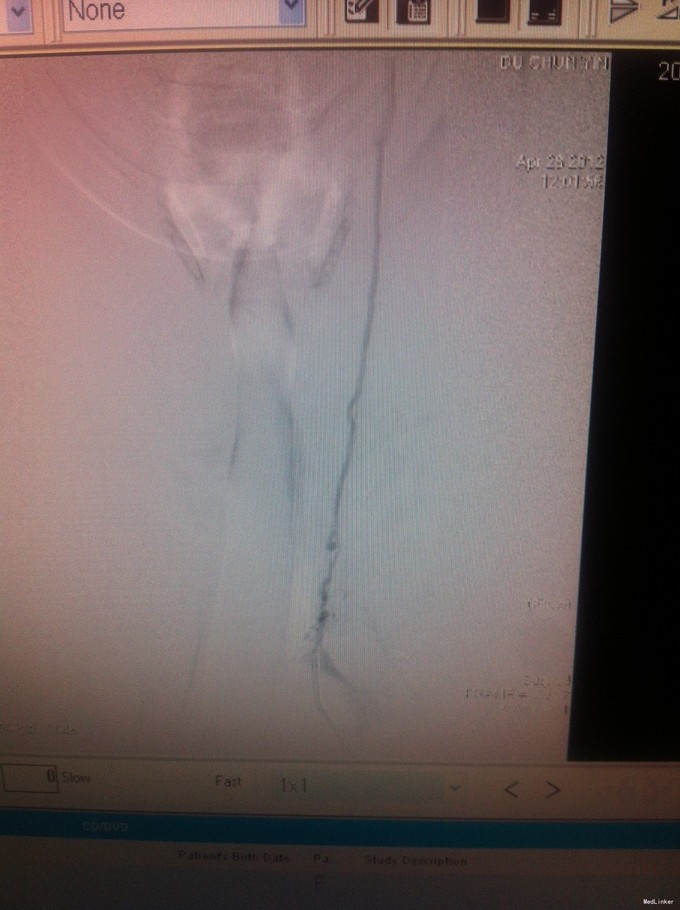

颈总动脉全程狭窄病例一例

动脉狭窄 颈总动脉狭窄

1、眩晕综合征 2、左侧颈总动脉狭窄

随访:该患者拟每三月复查头颈部动脉CTA,定期复查血脂、血糖、血压等情况。目前使用双抗加立普妥治疗。 讨论:患者颈总动脉狭窄、可否行支架植入治疗,个人觉得不可取,请各位专家多提宝贵意见,谢谢。